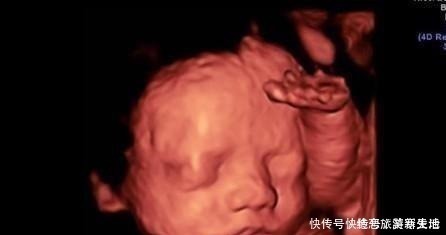

怀孕期间免不了要做好几次b超,每次都很重要,其中有一次就是在怀孕六个月左右的排畸检查。在有条件的地方一般都是做四维彩超,这样能够看得更清楚,更清晰。

1.实时观察胎儿动态运动,检查胎儿生长发育情况。在怀孕期间,孕妈妈可以通过四维彩超得知胎儿在宫内的一些动态情况。比如说,通过四维彩超能够清楚的看到胎儿在宫内吞吐羊水,眨眼睛,吮吸手指,做鬼脸等动作。医生还可以通过四维彩超更清楚的看得到胎儿的发育情况,比如说血管畸形,体表畸形,内脏畸形等等,提前得知胎儿是否有唇裂,脊柱裂,骨骼发育不良,先天性心脏病等疾病,做到早知道早干预早治疗。2.图像清晰逼真。四维彩超相对于三维彩超更高清更精确,所以看起来更清晰,很多孕妈妈在做四维的时候就可以清晰地看到胎儿的五官,可以初步的判断一下胎儿到底长得像准爸爸还是准妈妈,所以,四维彩超也成为胎儿人生中的第一张照片。而不像二维一样,在大部分人看来就是黑坨坨的一片。